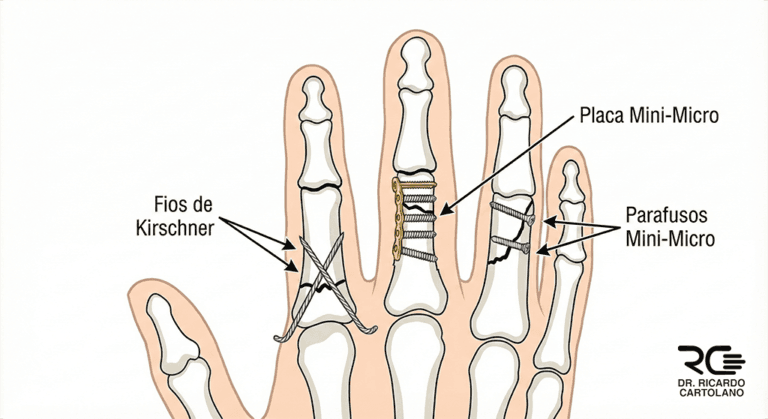

Cirurgia

A cirurgia é necessária quando a fratura é considerada instável ou desviada. O objetivo é realinhar os ossos (redução) e fixá-los para que não saiam do lugar.

As indicações mais comuns para cirurgia são:

Fraturas instáveis: Que tendem a sair do lugar mesmo com imobilização.

Fraturas desviadas ou anguladas: Quando o osso está “torto”.

Fraturas rotacionais: O dedo “gira” (o sinal de alerta que mencionamos).

Fraturas articulares: Quando a quebra afeta a superfície lisa da junta, exigindo um alinhamento perfeito.

Fraturas expostas: Quando o osso perfurou a pele.

A cirurgia de fixação pode ser feita com o uso de fios de metal (pinos), mini-parafusos ou mini-placas. O objetivo desses implantes é estabilizar o osso para permitir que o paciente inicie a Terapia da Mão o mais cedo possível. O procedimento é feito com anestesia (geralmente bloqueio do braço) e sedação.

Vou ficar com os pinos ou parafusos da cirurgia para sempre? Depende. Mini-parafusos e placas costumam ficar para sempre. Já os fios de metal (pinos) são quase sempre temporários, sendo retirados após 3 a 4 semanas, muitas vezes no próprio consultório.